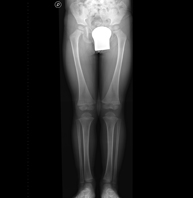

- Telemetry (Lower Limbs)

This technique uses X-ray rendered imaging to examine both lower limbs in their entirety, especially assessing the presence of dysmetria between the two.